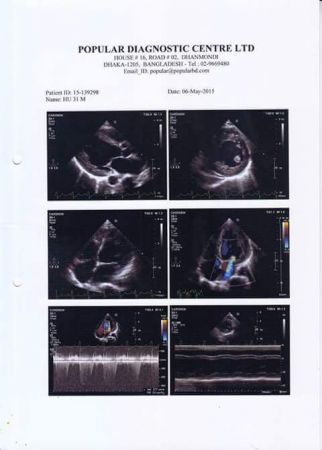

পুনশ্চঃ উনি কলকাতার BLK Hospital এ ভর্তি আছেন।